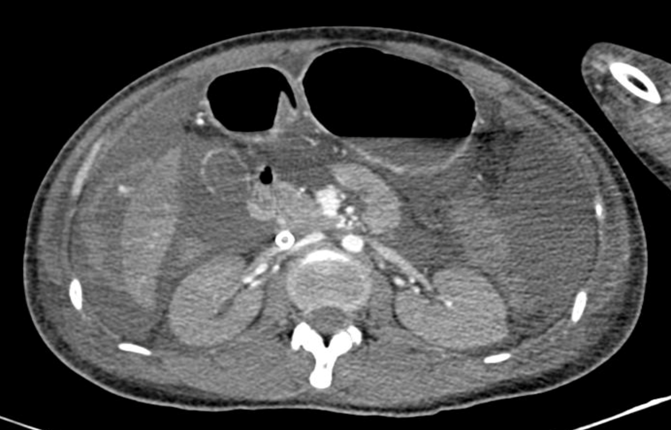

Dịch ổ bụng lượng nhiều, nghi ngờ chảy máu ổ bụng trên phim chụp cắt lớp vi tính. Ảnh: BVCC

Ngay lập tức, bệnh viện đã liên hệ khẩn cấp với Bệnh viện Truyền máu Huyết học TP.HCM và phát động hiến máu trong nội bộ nhân viên y tế để cứu bệnh nhân. Qua siêu âm và chụp CT, các bác sĩ xác định ổ chảy máu nằm tại vùng gan.